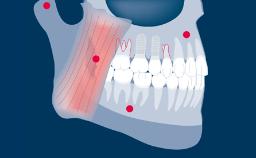

Implant dentistry has evolved considerably since early treatment protocols in which the positioning of implants was not considered critical to a successful outcome.

In this surgically driven approach, implants were placed where there was sufficient bone to support them, and the emphasis was on the functional outcome.

Templates to guide accurate three-dimensional implant placement are critical to achieving such an outcome. This ITI Learning Module will discuss routine use of templates in implant therapy.